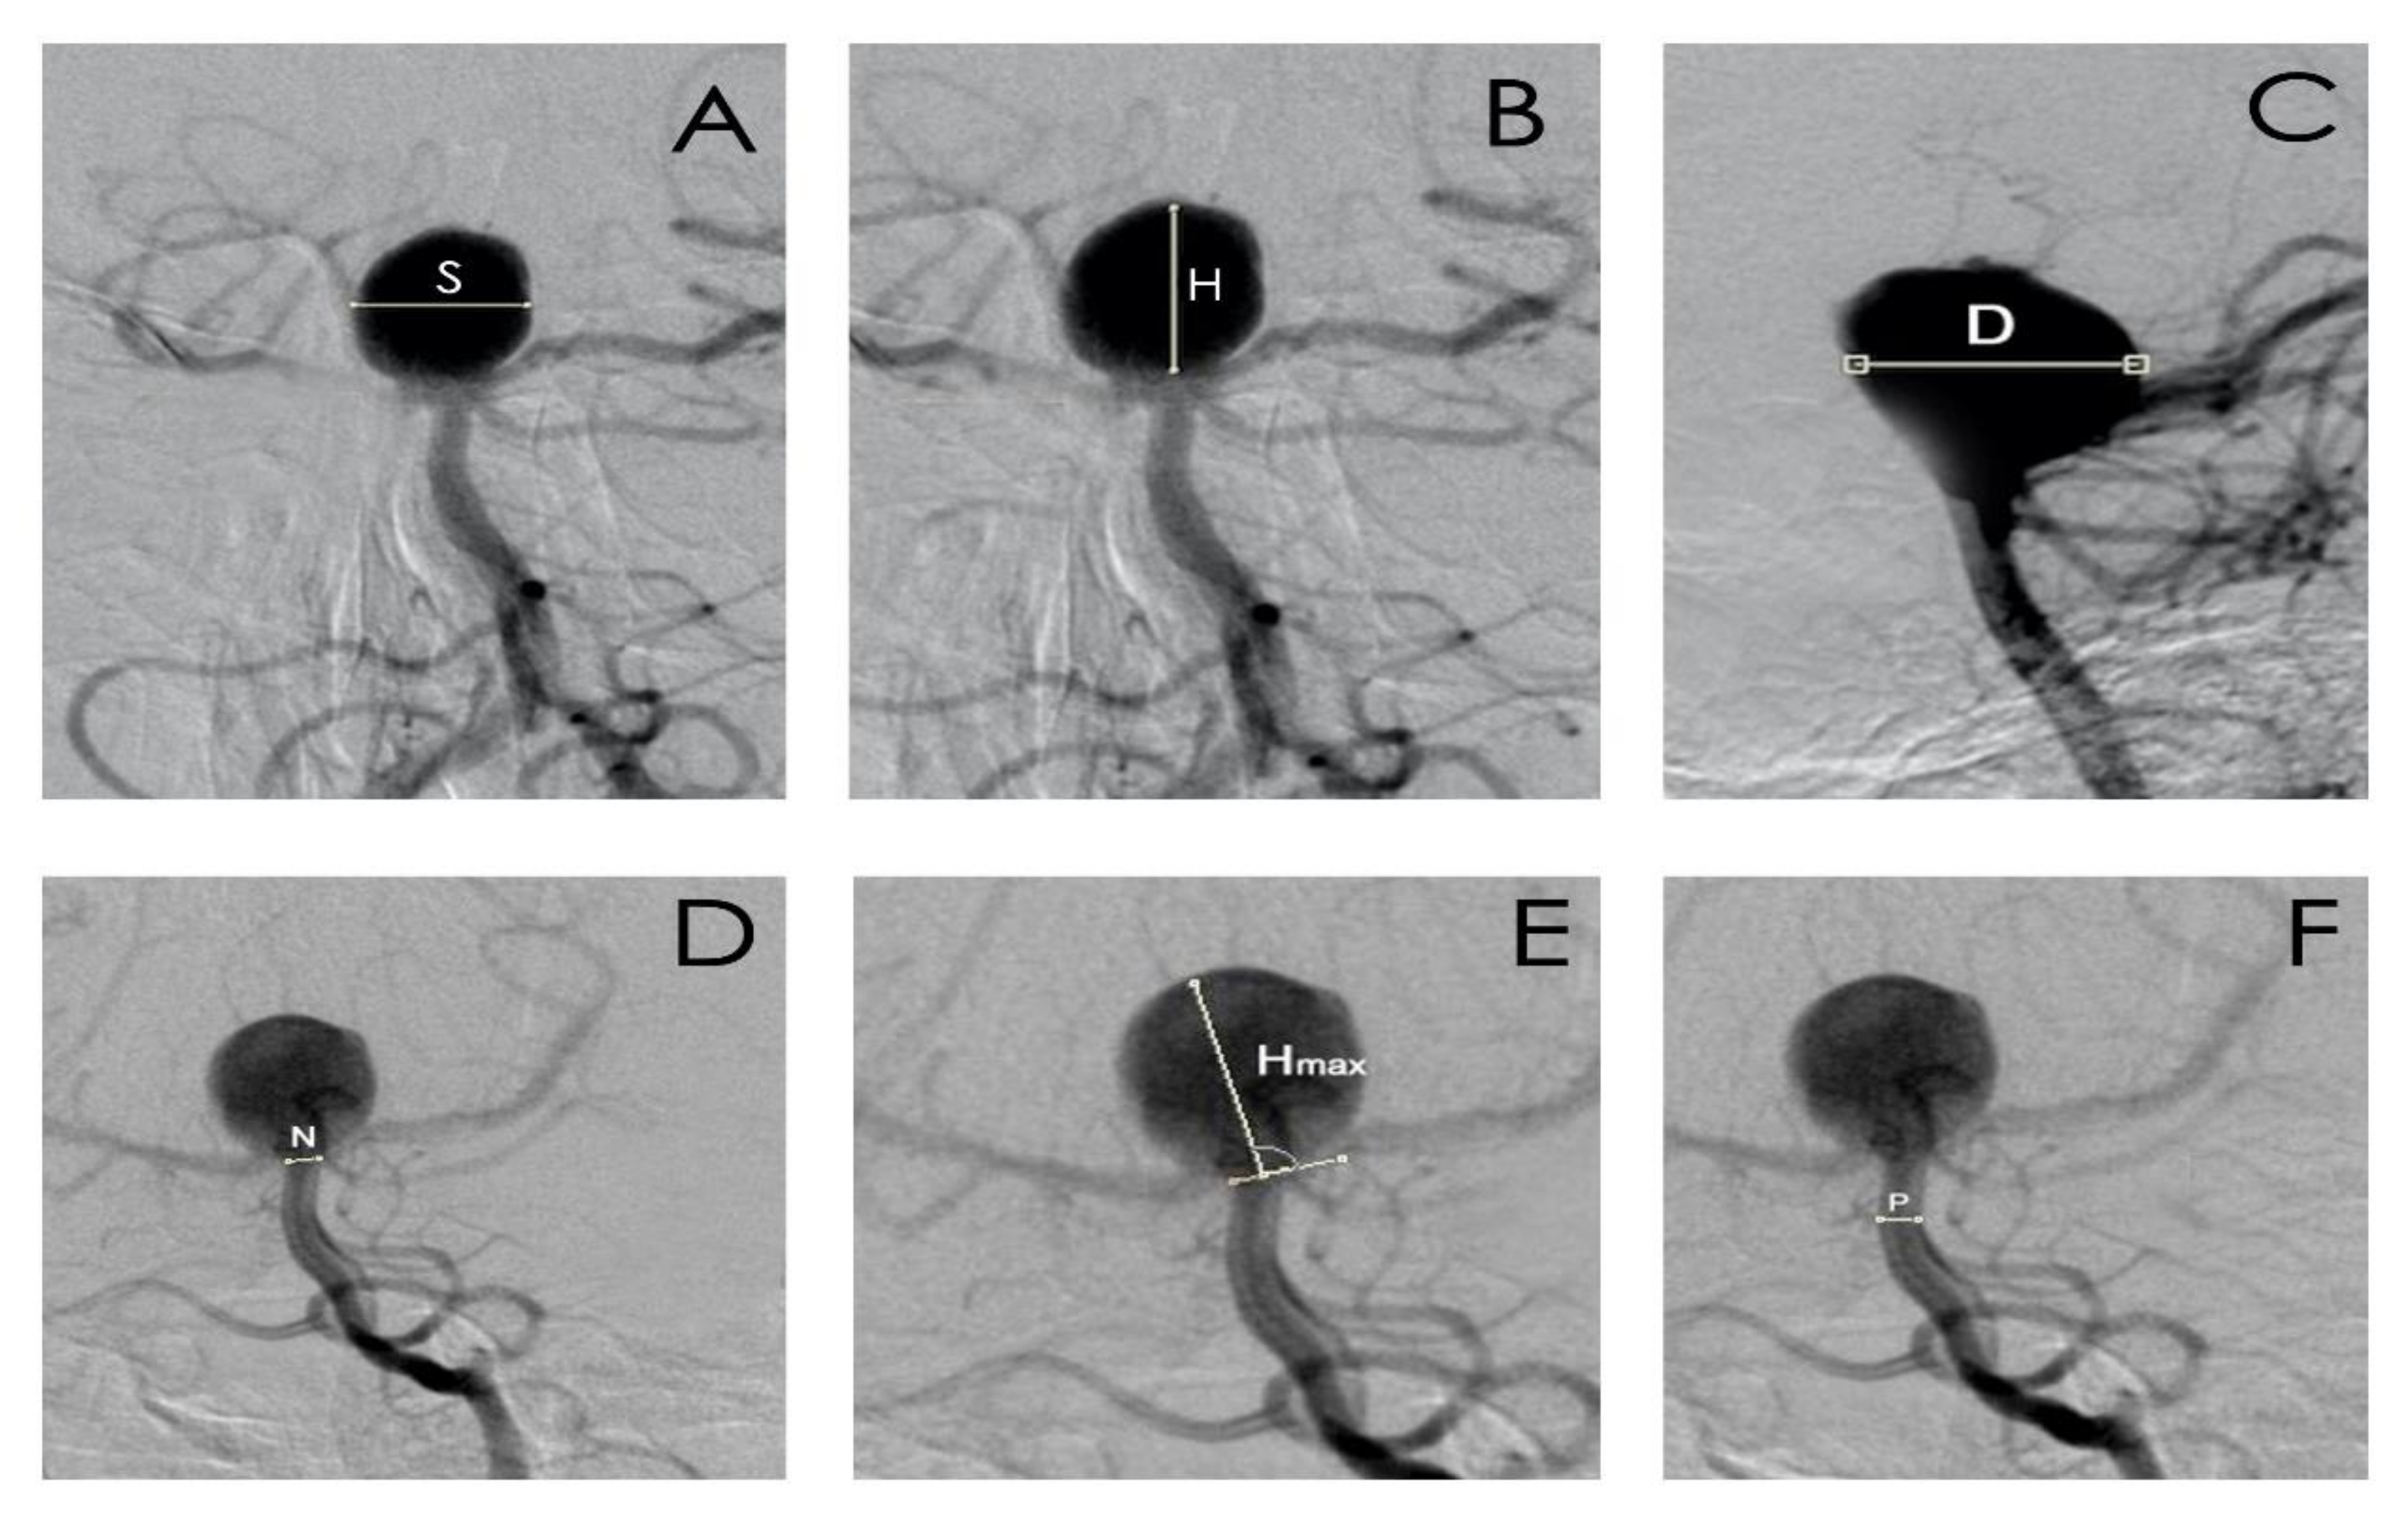

- aneurysm dome height (H), width (S), and depth size (D);

- aneurysm neck size (N);

- parent artery size (P);

- the largest aneurysm dimension perpendicular to the neck (Hmax);

- aspect ratio (AR), defined as the maximal perpendicular height (the largest perpendicular distance from the neck of the aneurysm to the dome of the aneurysm) divided by neck width;

- size ratio (SR), defined as maximum aneurysm height (between the center of the aneurysm neck and the greatest distance to the aneurysm dome), divided by the parent artery diameter;

- the index determining the ratio of aneurysm neck width to diameter of the parent artery.